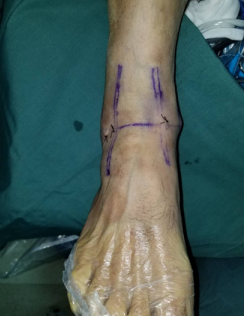

手术入路——两个0.5厘米小孔

石院长给他做了仔细检查,结合片子,确诊为“右踝外侧韧带损伤”。两天后,石院长李亮医生给患者进行了踝关节镜下右踝探查清理+距腓前韧带修复手术。

术中,探查见关节腔大量增生病变滑膜组织,距骨软骨面多处软骨剥脱变性,明显的外侧副韧带损伤后继发关节炎表现。手术医生在踝关节镜下刨削刺激病变的距骨软骨,打入锚钉固定距腓前韧带,圆满完成手术。